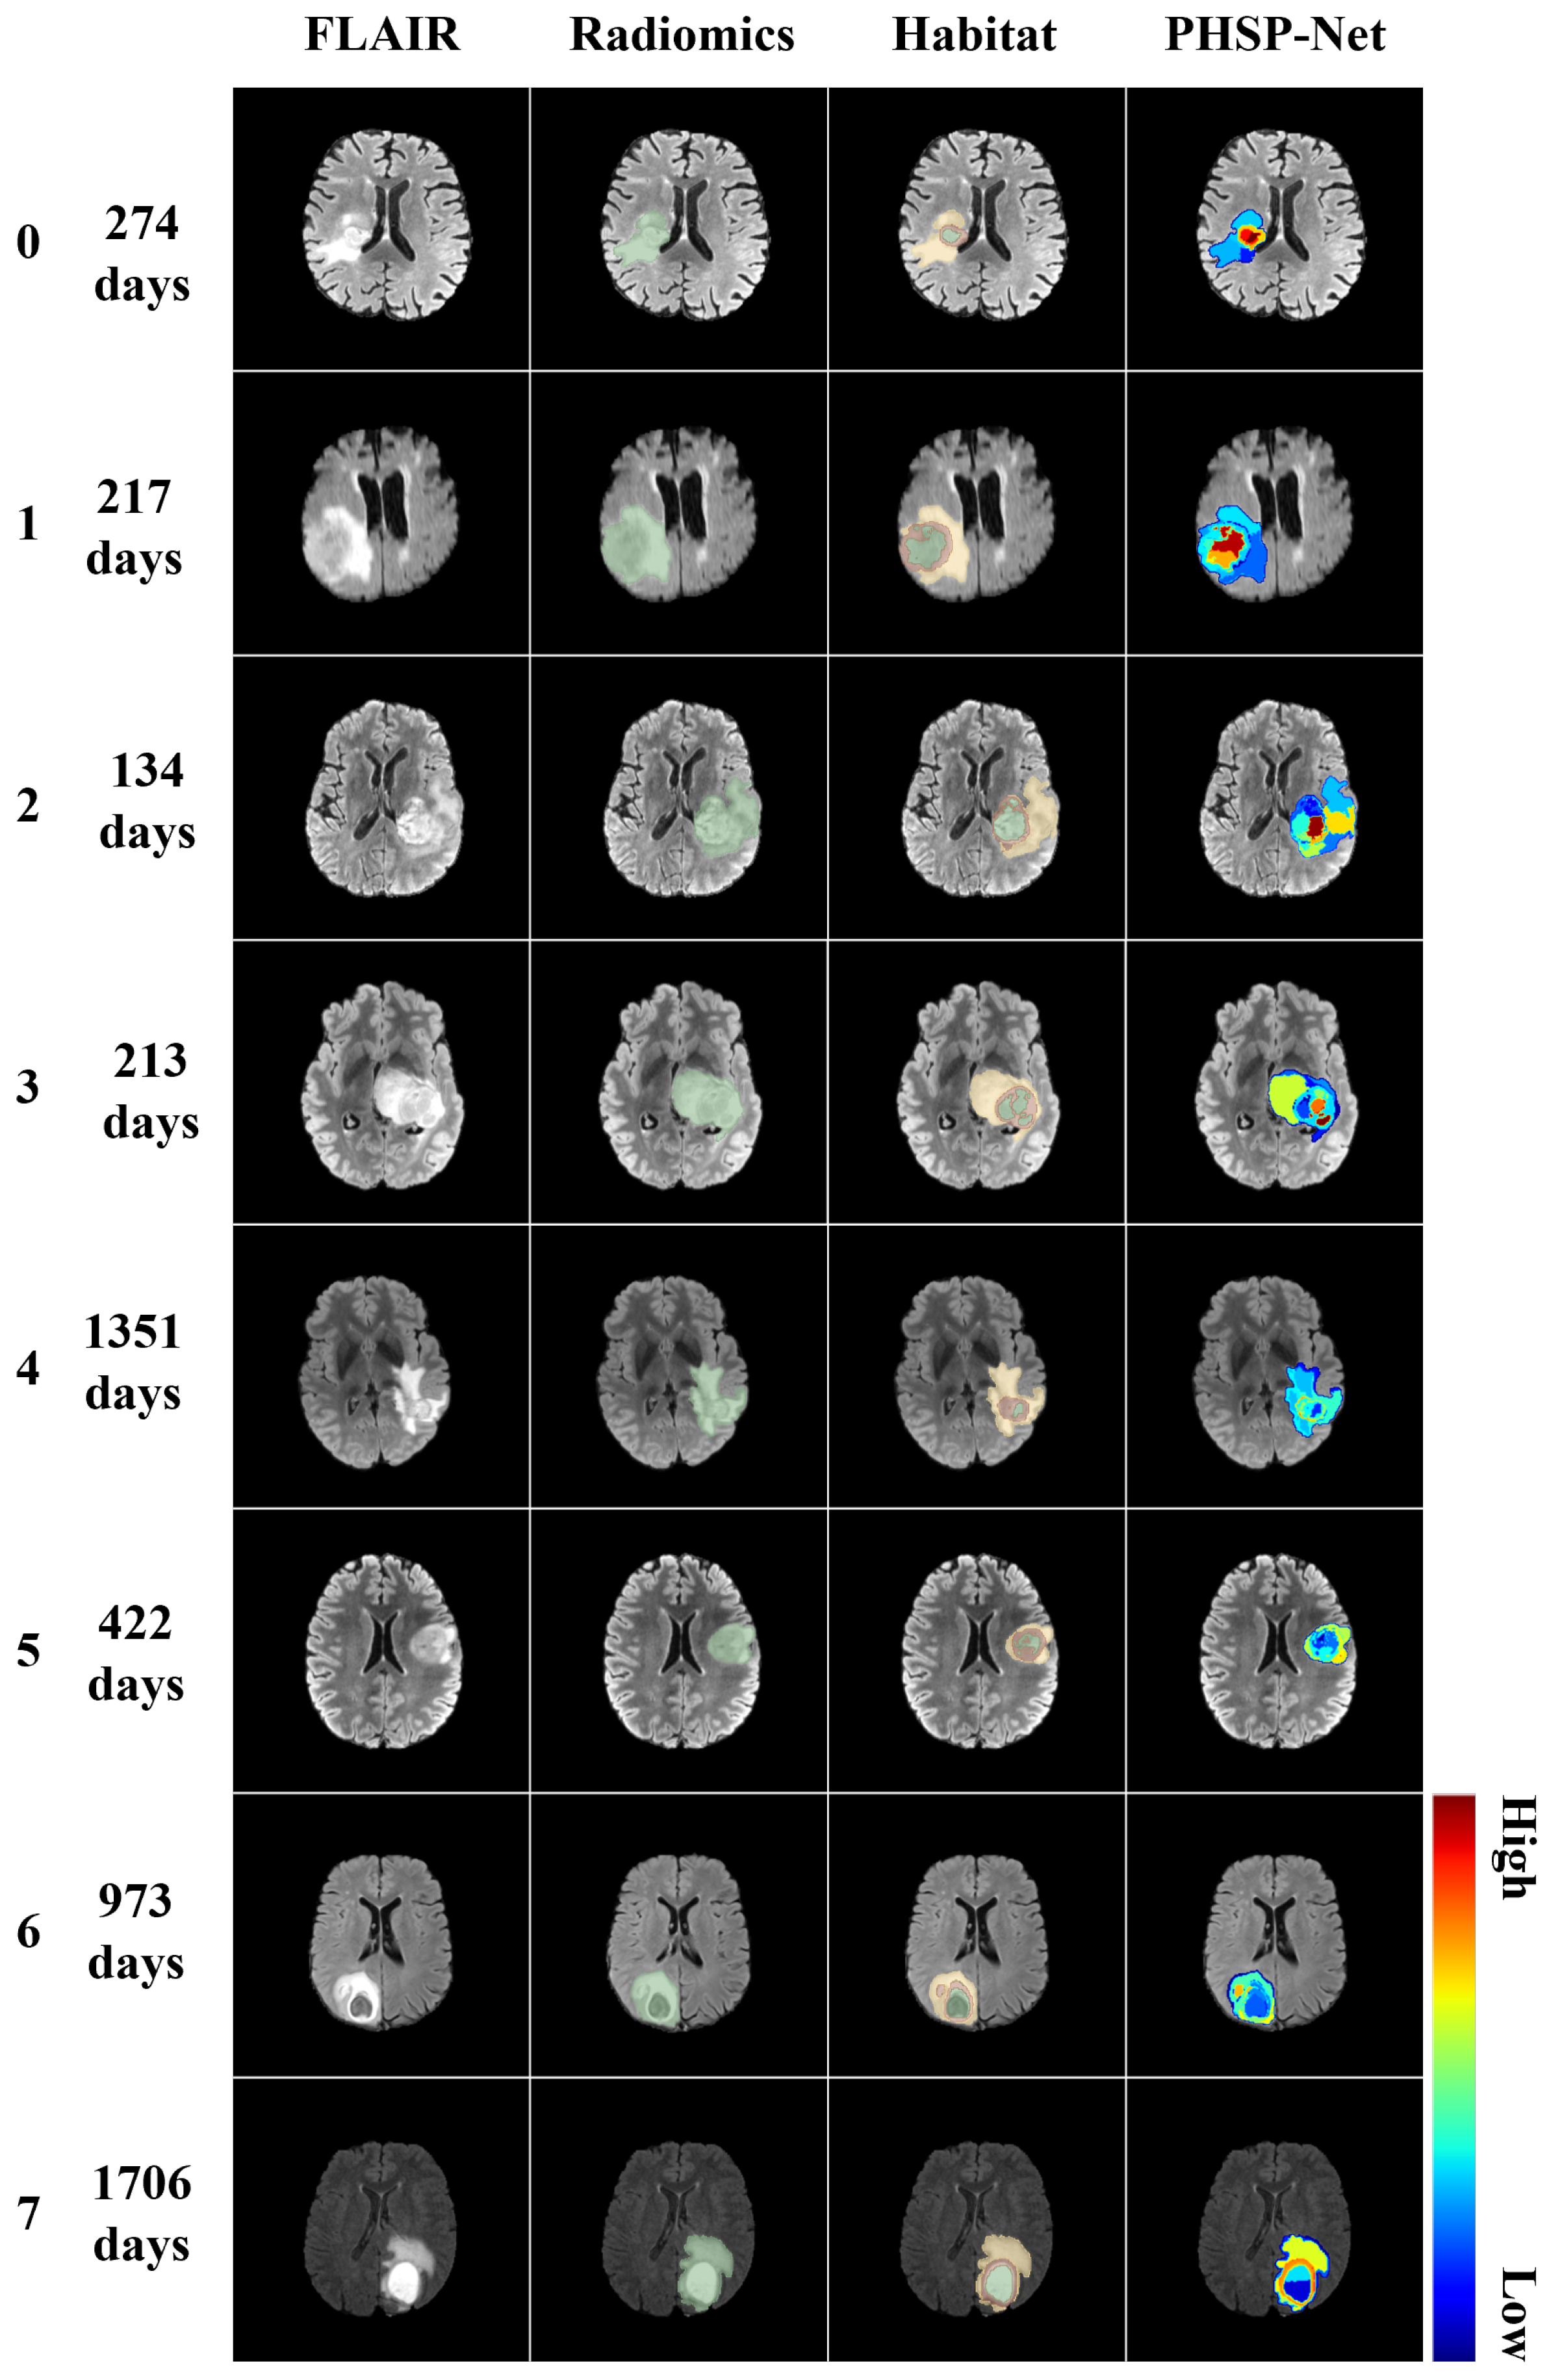

3.4. Model Visualization